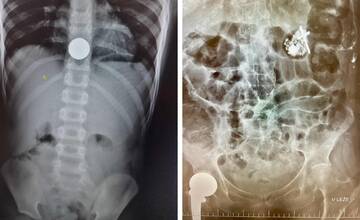

Na urgentnom príjme v Poprade riešia aj kuriozity: Chlapec prehltol dve eurá, seniorka zasa ruženec